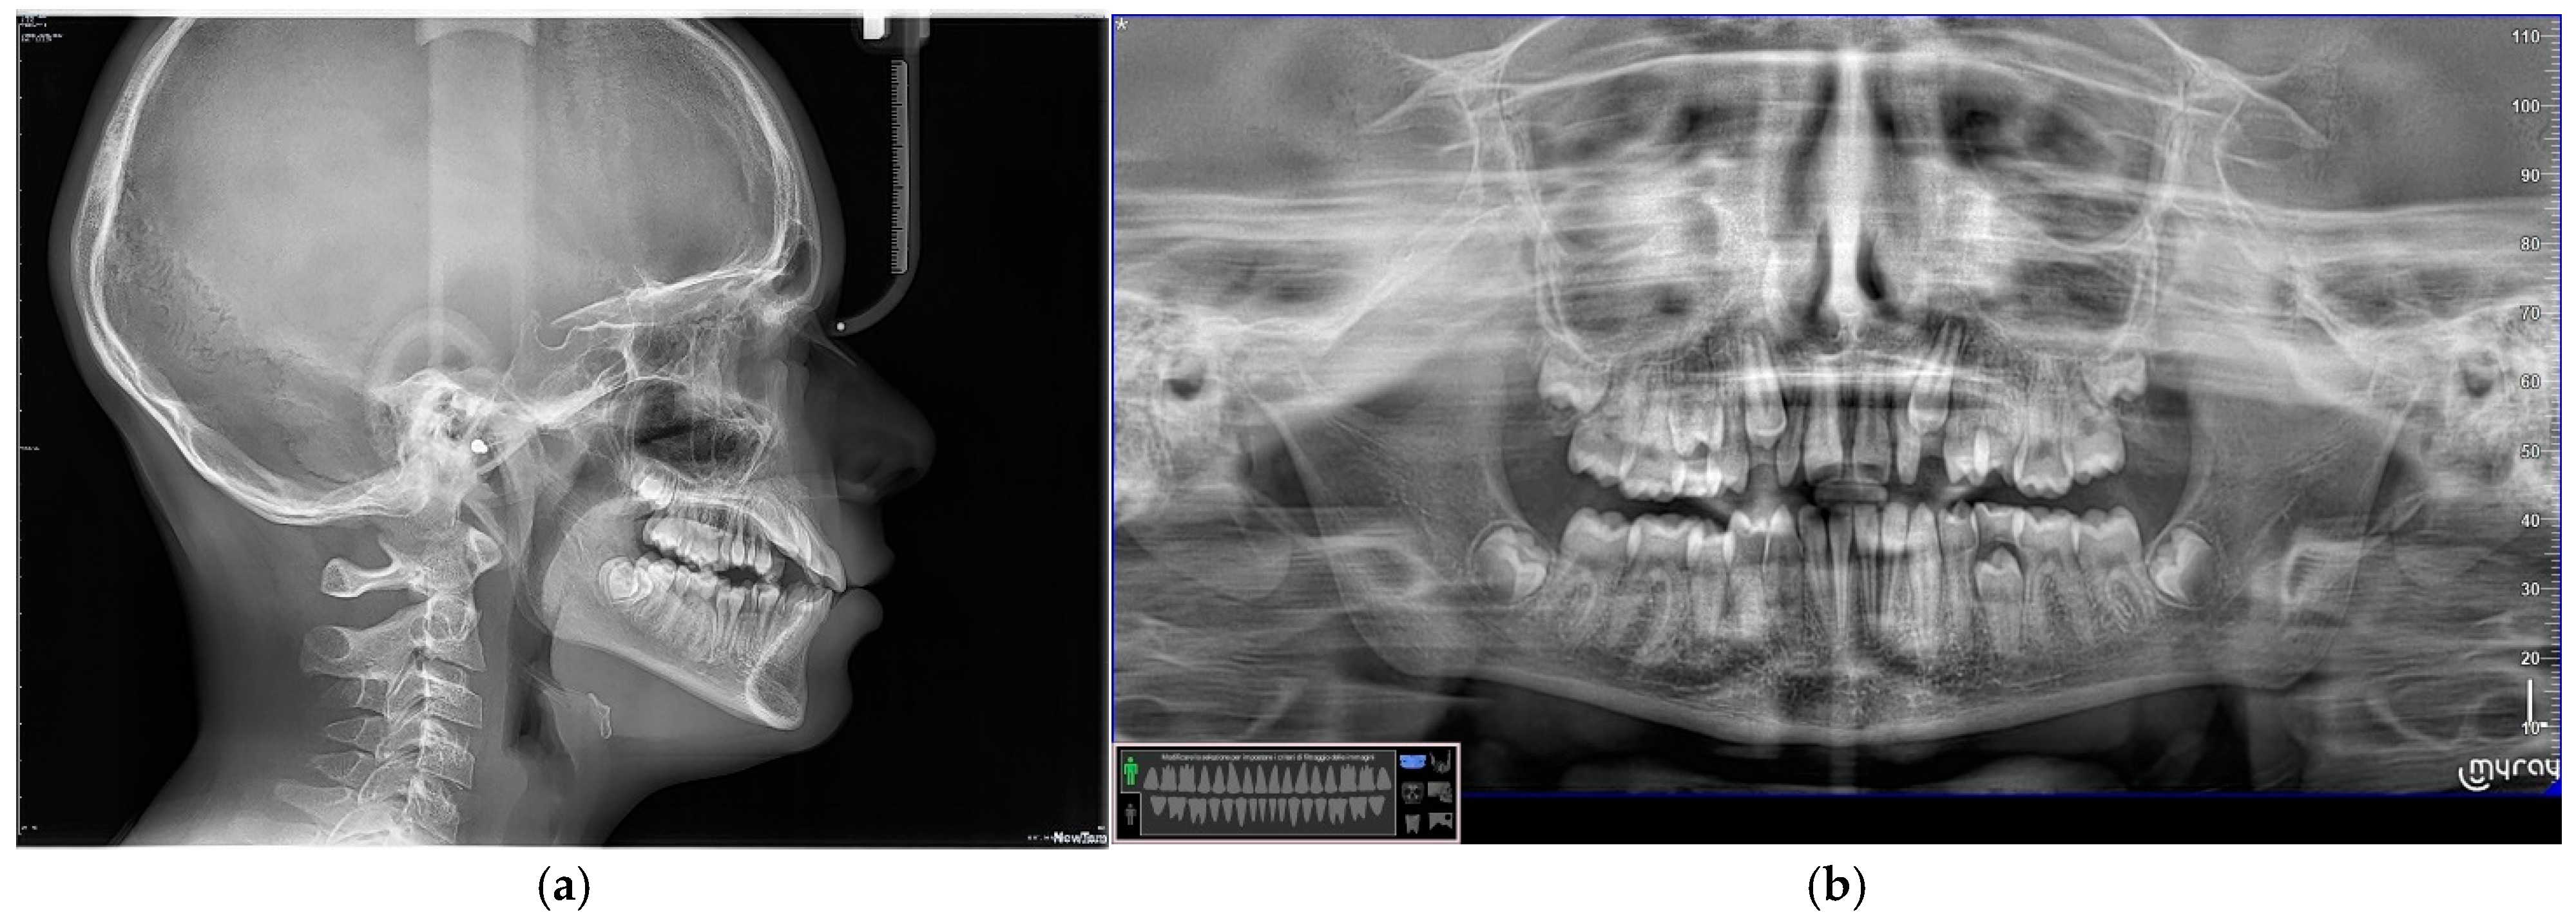

The diagnostic process involved collecting conventional orthodontic records, including photographic documentation, radiographic imaging, and dental casts. These records were systematically organised and analysed using digital software (Digital Smile Design—Keynote) platforms to ensure comprehensive data management (Figure 1). Subsequently, the software was utilised to assess and modify tooth dimensions and morphology digitally.

Figure 1.

(a) Frontal view of teeth with a slightly open mouth to elucidate the conoidal teeth (12 and 22). (b) Occlusal perspective of the patient’s maxillary arch. (c,d) Radiographic evaluations.